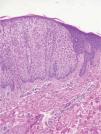

Con el posible diagnóstico clínico de liquen mixedematoso biopsiamos tres pápulas, siendo la imagen anatomopatológica similar en las tres. Se observaba una hiperplasia psoriasiforme, integrada por células grandes, de citoplasma claro (fig. 3), intensamente PAS positivo. La demarcación con la epidermis sana adyacente era muy nítida en las tres lesiones.